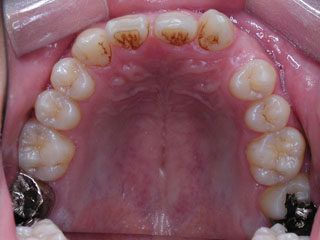

主訴:前歯の歯並び

診断名:開咬傾向を伴う叢生

年齢:14歳

使用した主な装置名:HG、TPB、マルチブラケット装置

抜歯/非抜歯および抜歯部位:抜歯(上顎左右第一小臼歯)

治療期間:動的処置1年10か月、経過観察3年

費用の目安:90~140万円

リスク、副作用:抜歯によるリスク、マルチブラケット治療に伴う歯根吸収など偶発症が発生するリスクがある。

過蓋咬合が見られます。下顎の前歯がほとんど見えない状態に隠れています。タイプとしては2級2類と呼ばれる不正咬合です。上下共に中程度以上の叢生が見られますが、上顎前突の改善のために上顎のみ小臼歯抜歯としました。